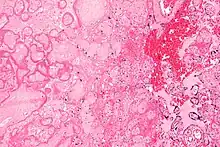

| Micrograph of a placental infarct. H&E stain. | |

A placental infarction results from the interruption of blood supply to a part of the placenta, causing its cells to die.

Small placental infarcts, especially at the edge of the placental disc, are considered to be normal at term. Large placental infarcts are associated with vascular abnormalities, e.g. hypertrophic decidual vasculopathy, as seen in hypertension.[1] Very large infarcts lead to placental insufficiency and may result in fetal death.

Maternal floor infarcts are not considered to be true placental infarcts, as they result from deposition of fibrin around the chorionic villi, i.e. perivillous fibrin deposition.